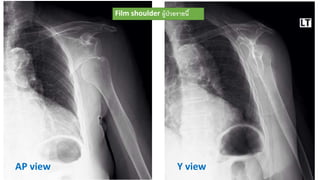

• Film Lt shoulder in AP view , lateral scapula Y view

Y viewAP view

Film shoulder ผู้ป่วยรายนี้

Finding

• Lt. anterior shoulder dislocation , subcoracoid type

• No fracture seen

Investigation • Film Ltshoulder in AP view , lateral scapula Y view

Y viewAP view Filmshoulder ผู้ป่วยรายนี้

Finding • Lt. anteriorshoulder dislocation , subcoracoid type • No fracture seen